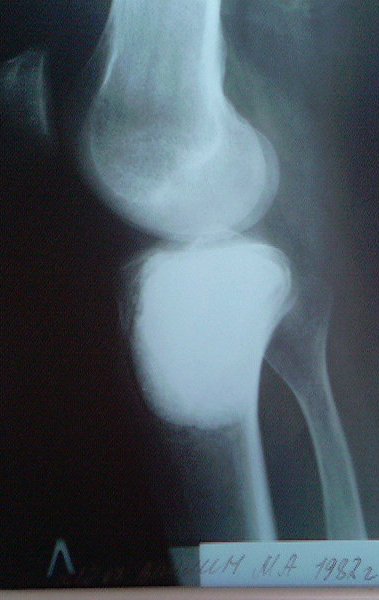

[Ortho] пластика мыщелка б\б кости

около года назад больному 25 лет по поводу литической опухоли мыщелка

б\б кости ( ОБК?)с выраженным болевым синдромом была произведена

расширенная открытая биопсия, экскохлеация опухоли. В связи с

неясностью диагноза до операции и отсутствия аллокости в тот момент

интраоперационно было выполнено экспресс протезирование дефекта

мыщелка акриловым цементом. Верхней стенкой дефекта была визуально

неповрежденная суставная поверхность. Хрящевая пластина провисала -

была выведена на уровень и "подперта" цементным спейсером. Больной

осмотрен через год - ходит не хромая, сустав абсолютно спокойный,

рентгенологически процедива опухоли нет. Хотелось бы услышать

предложения по пластике дефекта - сроки, вид материала. Честно говоря

боюсь трогать хрящ повторно.